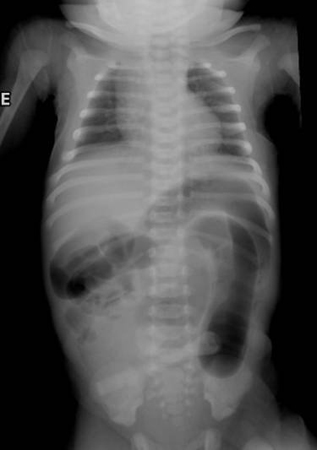

Enterocolite necrosante

neonatos prematuros com peso inferior a 1500 g; intolerância alimentar, apneia, letargia, fezes com sangue

Exame físico

distensão abdominal, sensibilidade, eritema na parede abdominal, hematoquezia, bradicardia

Primeira investigação

- radiografia abdominal:

alças do intestino dilatadas, pneumatose intestinal, gás na veia porta, ar livre, alça intestinal presa; ausência do padrão de gases normal no intestino